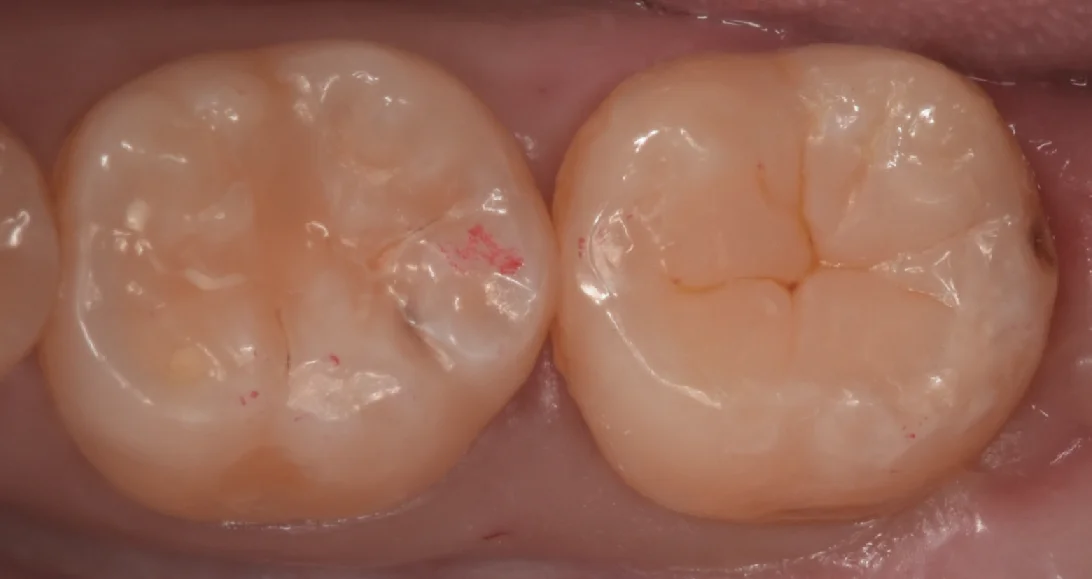

さて、詰め物を取り切ったのがこちらになります。

案の定中に虫歯の取り残しがあったので、そちらも取り切っていますが、名残で若干の着色は残っています。

本来であればこの部分もしっかりと取っておいた方が接着としては有利なのですが、神経が非常に近かったため温存する方向にしました。